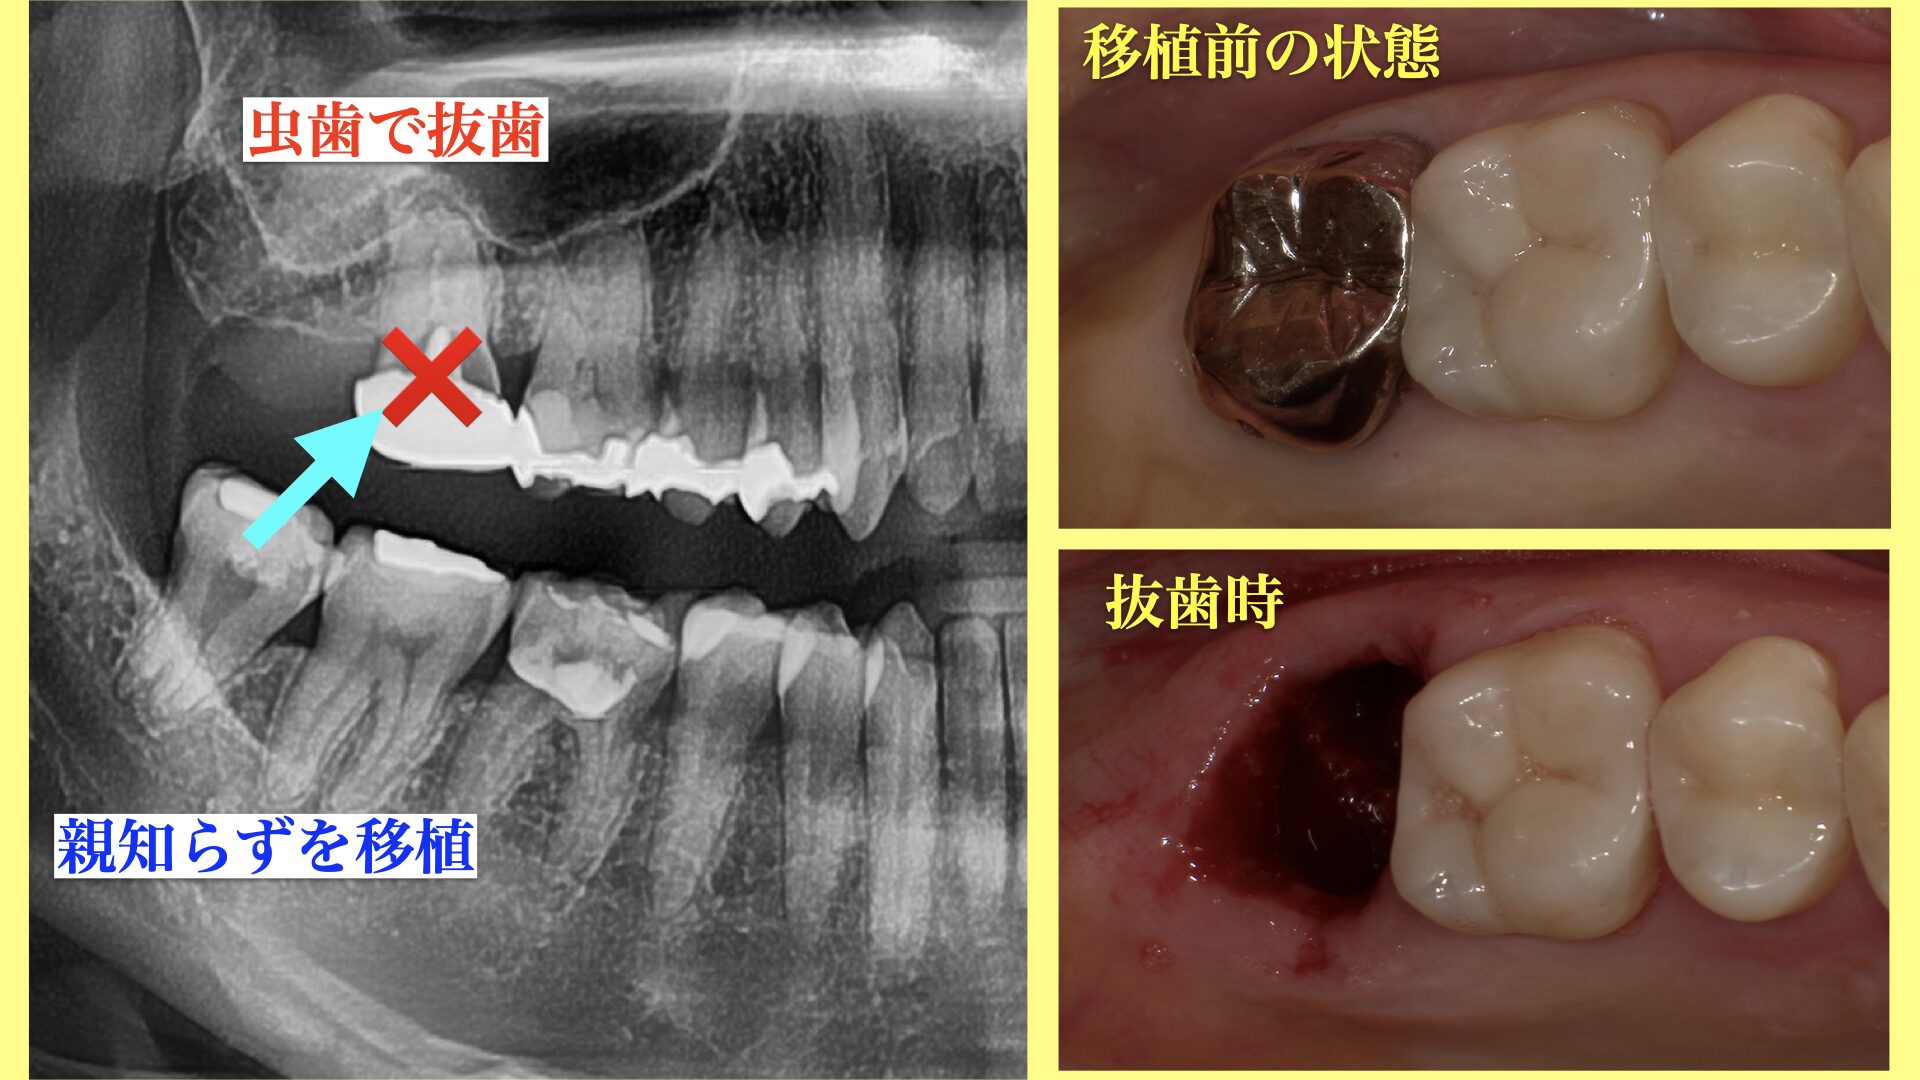

CASE 症例紹介

当院では、歯周病治療やインプラント治療、セラミック治療、審美治療など、様々な治療オプションを用いて、お口の中全体を管理しています。

院長が施術してきた症例をご確認のうえ、お気軽にご相談・ご来院ください。

歯周外科治療Periodontal surgery

基本的な歯周病治療のほか、歯周組織を再生する治療や、歯肉の移植なども行います。認知症をはじめとする、全身疾患の要因にもなる歯周病を原因から改善します。